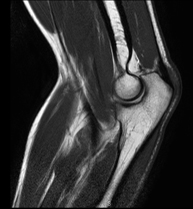

- Knee MRI

Examination to study joint injuries, such as meniscal tears and cruciate ligament tears (only detectable through this test), chondropathy or cartilage wear, and a multitude of other disorders resulting from sports activities and degenerative changes (osteoarthritis). It lasts approximately 18 minutes. It is a radiation-free procedure.